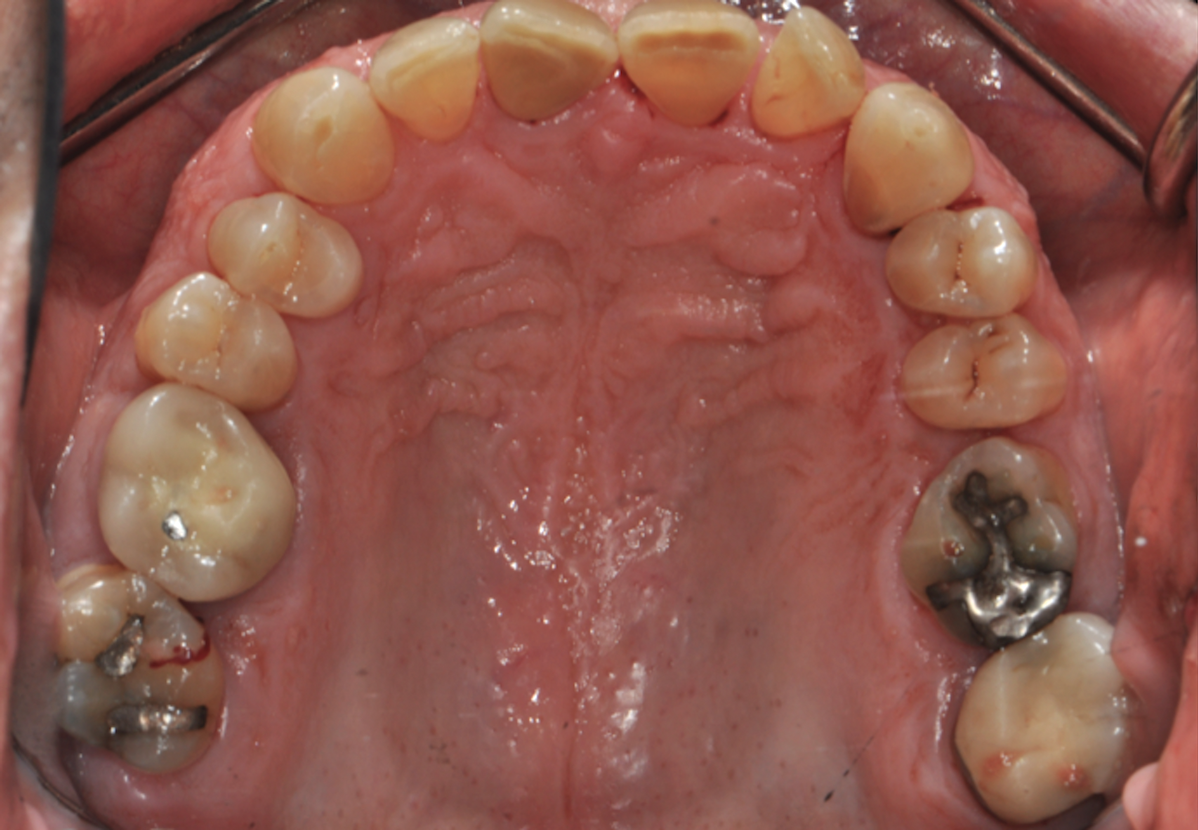

Fig 2. Pretreatment views: right lateral (Fig 2), frontal (Fig 3), and left lateral (Fig 4). Note: The maxillary right first molar (tooth No. 3) (Fig 2) would be identified as the most periodontally involved molar that was planned to be maintained.

Figure 2

Periodontal examination revealed generalized BOP and PDs up to 9 mm in the maxillary and mandibular molars with multiple furcations in each molar (Figure 2 through Figure 7). He presented with class I mobility in many posterior teeth and class II mobility in teeth Nos. 3 and 9 (maxillary right first molar and maxillary left central incisor, respectively). The periodontist decided to score tooth No. 3 for the PRS, as this was the most periodontally involved molar that was planned to be treated and maintained (Figure 2 and Figure 8). This tooth (maxillary right first molar = score 1) presented with probing depths of 7 mm (score 1); three total furcation invasions (score 3) (mesial [degree II furcation], buccal [degree I furcation], and distal [degree II furcation]); and a class II mobility (score 2). The total PRS for tooth No. 3 was 8, representing a "guarded" prognosis. Based on this score, the likelihood of not losing any teeth to periodontal disease for 15 years was 81%, and for 30 years the likelihood was just 56% (Figure 9).7